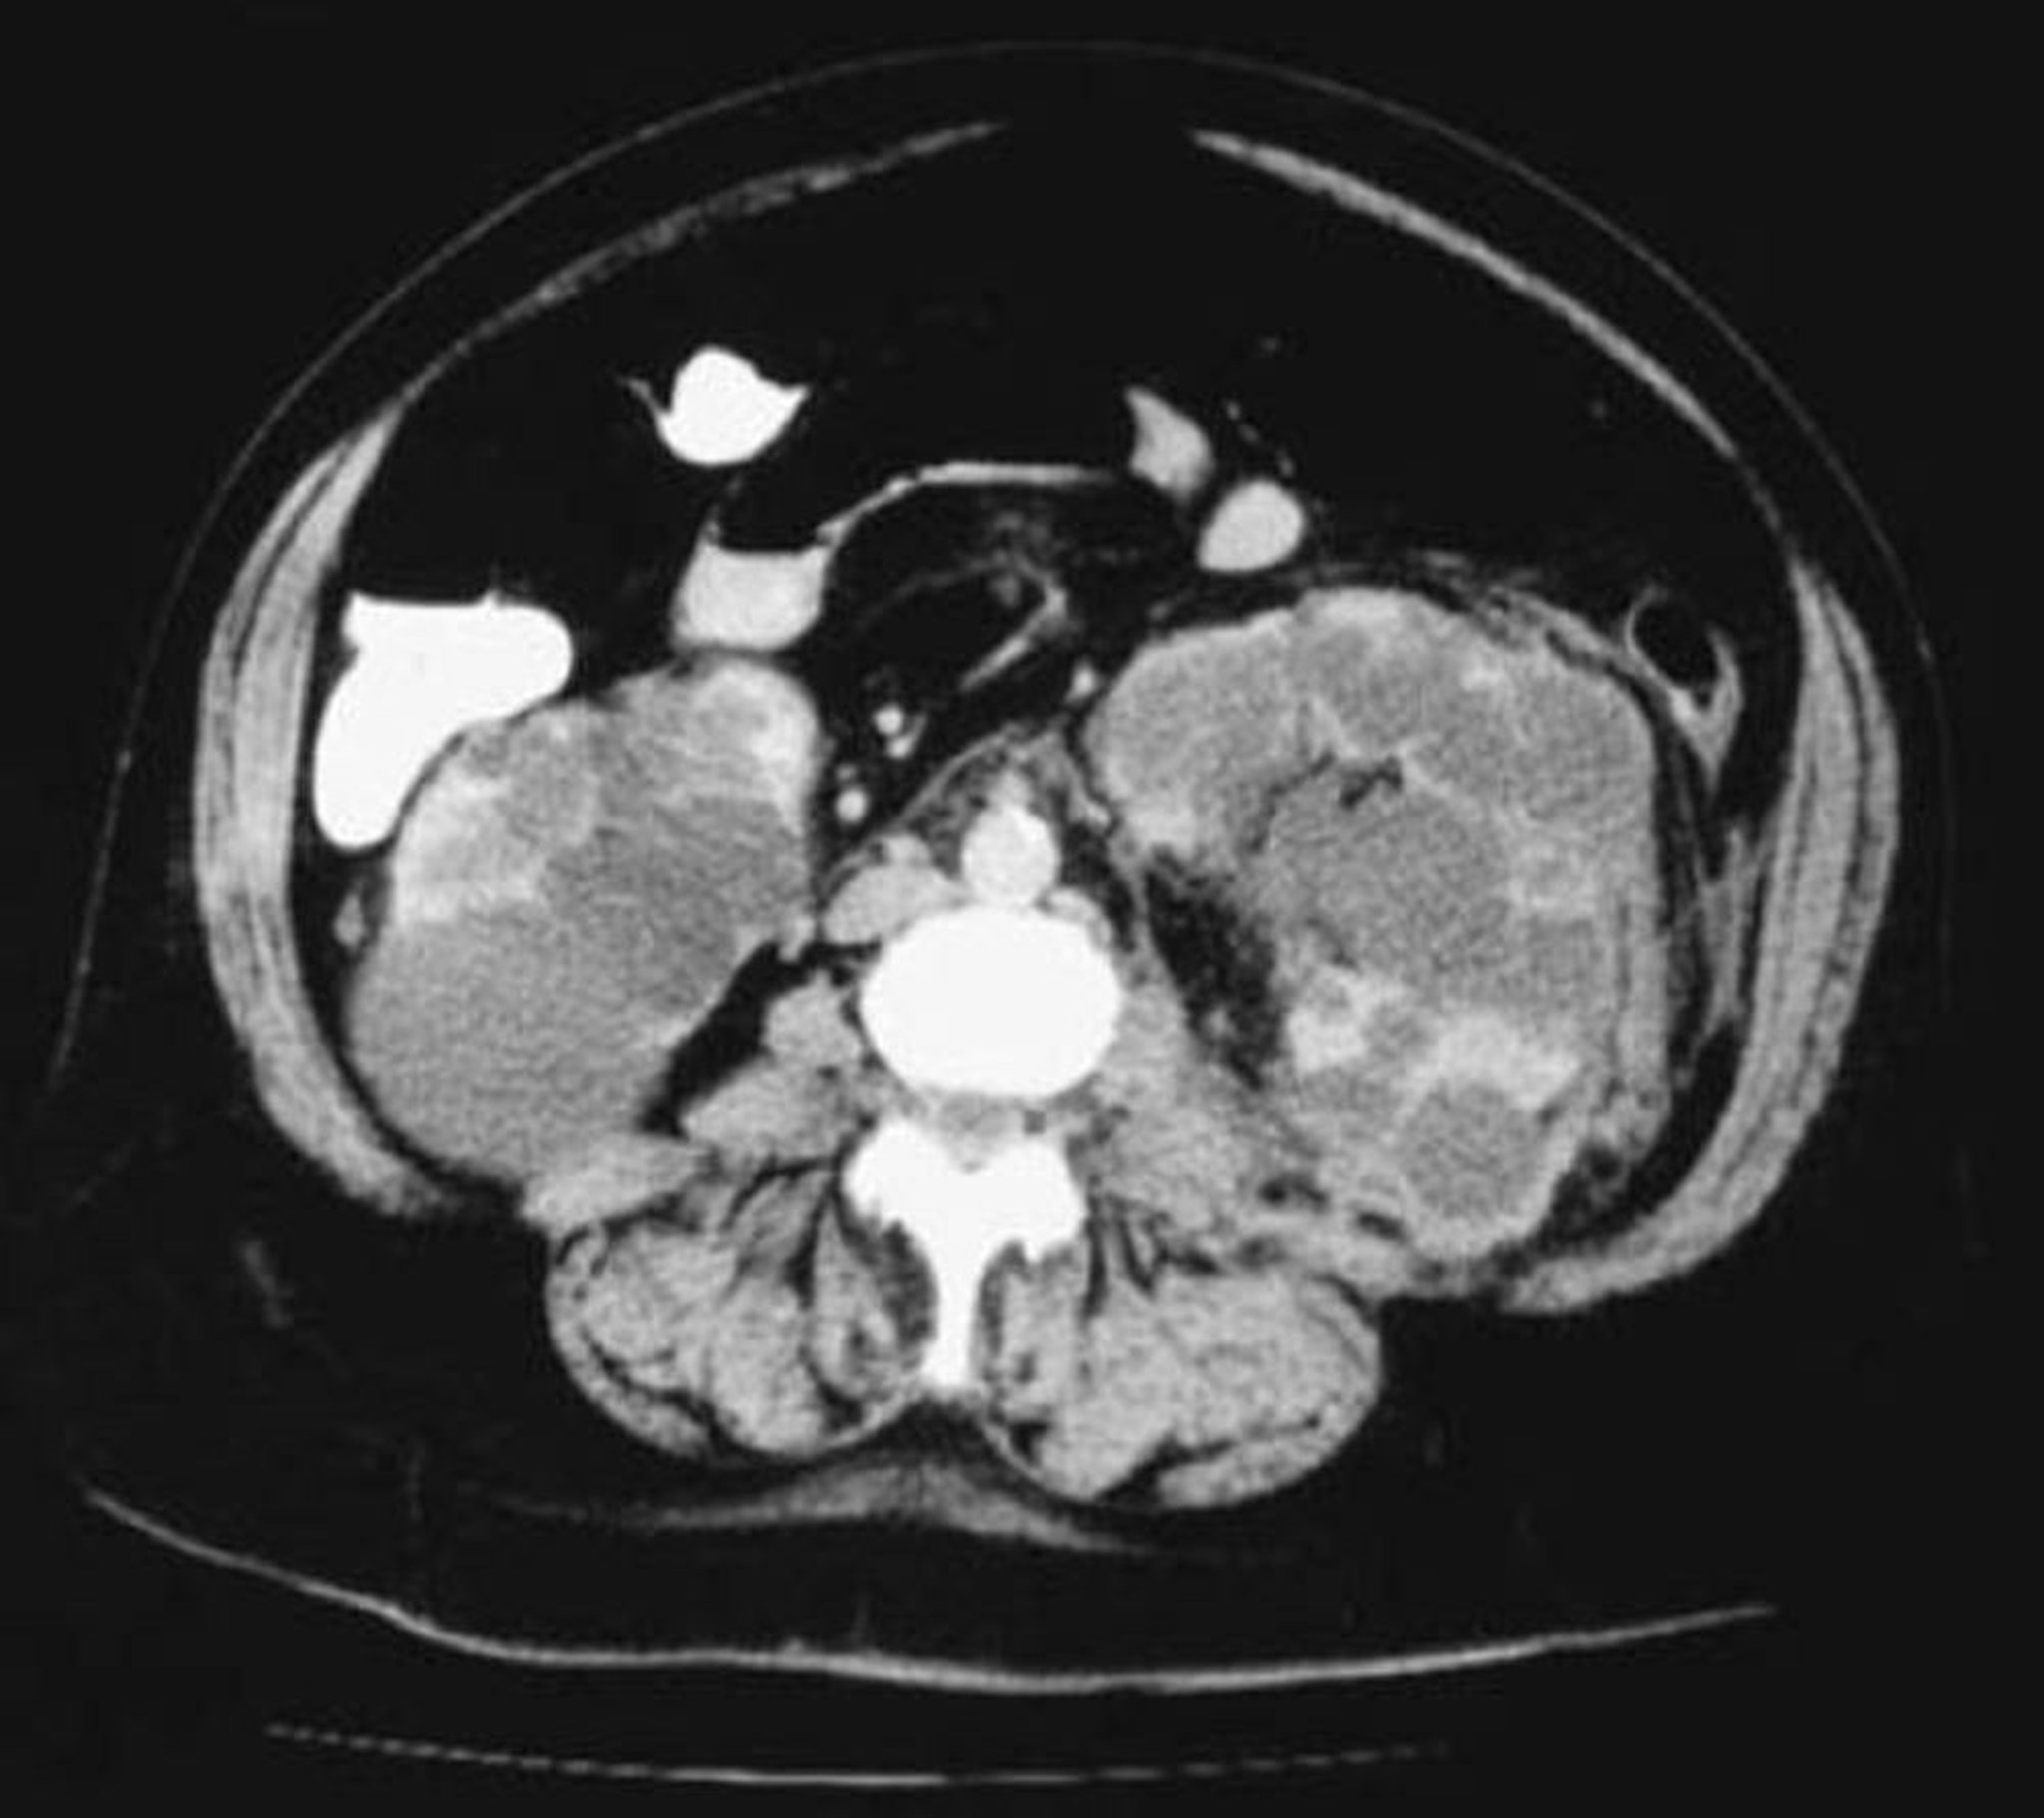

TC de vista axial de los riñones poliquísticos

Esta TC de los riñones muestra numerosos quistes de tamaño variable. Queda poco parénquima renal.